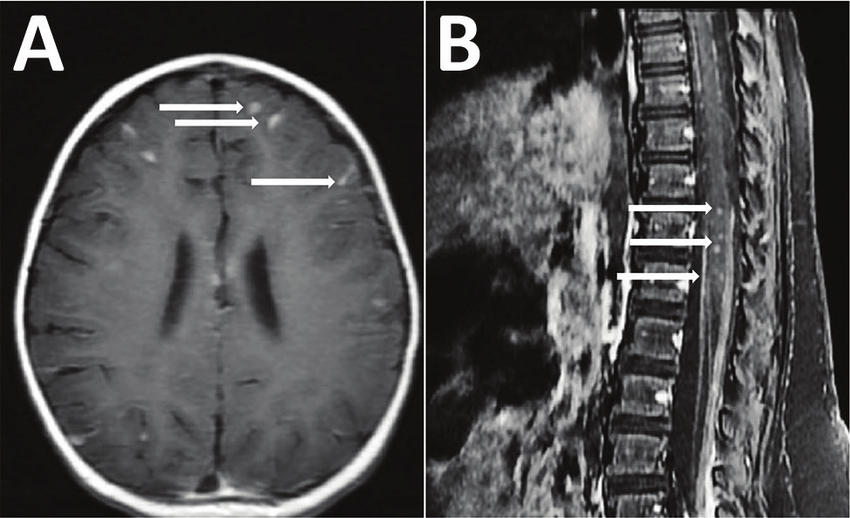

→ 뇌에서 살아있는 기생충 발견

이 기생충은 쥐폐선충(Angiostrongylus cantonensis) 계열로, 주로 쥐·달팽이·민달팽이 등에 기생합니다.

- 뇌 또는 척수로 침입

- 염증·신경 증상 유발